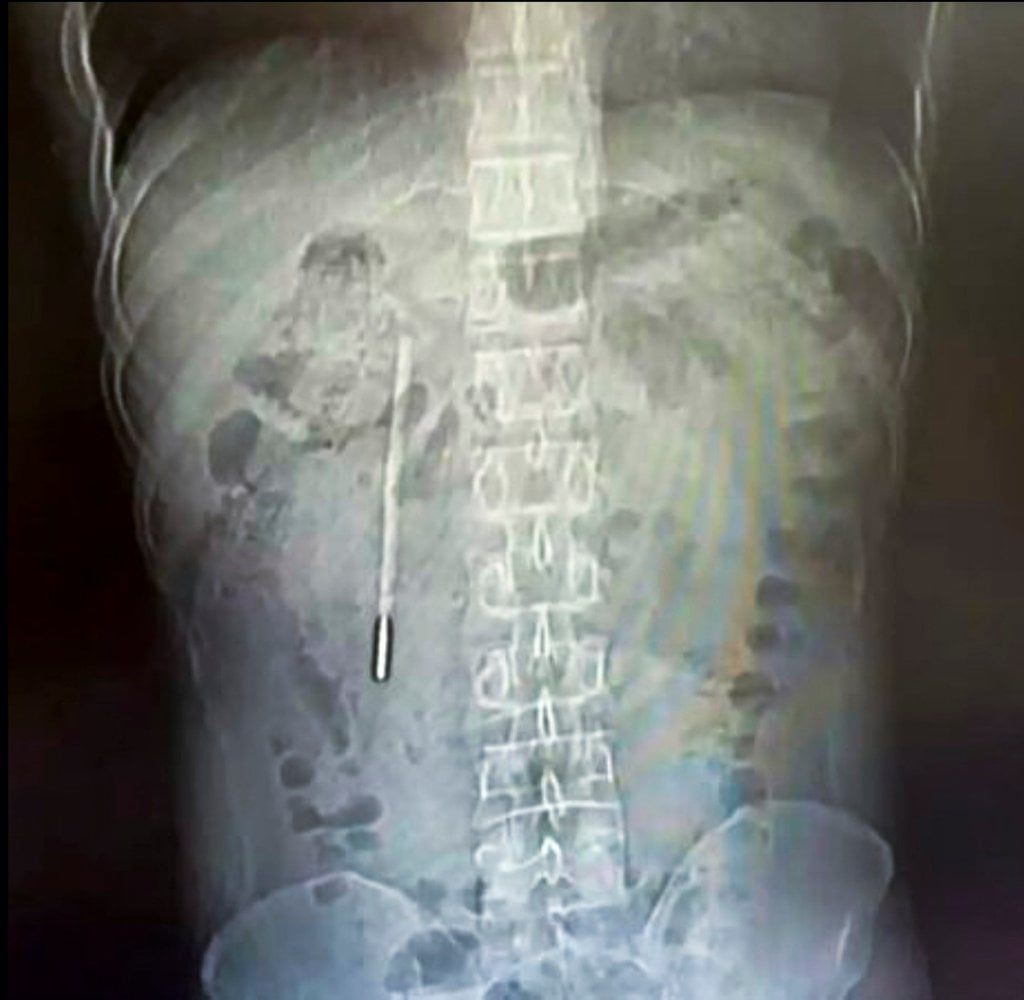

แพทย์ทำการเอกซเรย์ร่างกาย ผลสแกนเผยให้เห็นสิ่งแปลกปลอมอยู่ในลำไส้เล็กส่วนต้น แพทย์คาดการณ์ว่าสิ่งนี้คือปรอทวัดไข้ ปลายของปรอทกดทับผนังลำไส้โดยตรง มีความเสี่ยงสูงที่จะทำให้ลำไส้ทะลุรวมถึงเกิดภาวะเลือดออกในอวัยวะภายในอย่างรุนแรง